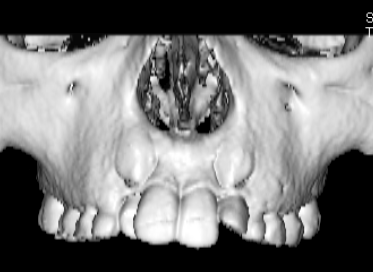

治療法:上顎急速拡大装置+クリアスナップ+フェイスマスク+上顎3番は開窓牽引CT写真にて位置確認

FX(フェイシャルアキシス)は85度なので東洋人の平均値に近く、下顎が前方に過剰成長するリスクは強くはありません。

しかしやはり上顎は劣成長で、下顎が優位な状態ではあります。

骨年齢は実年齢よりも低めなので、今後下顎の旺盛な成長が見込まれます。

検査時のレントゲン分析では、上下顎の関係は、上顎の劣成長があり下顎前突傾向という値がでておりましたが、前歯ジャンプ後はフェイスマスクの効果もあり、上下顎の関係は正常化しています。

上顎が若干優位になっていますので、今後の下顎の成長のための貯金になっているくらいです。